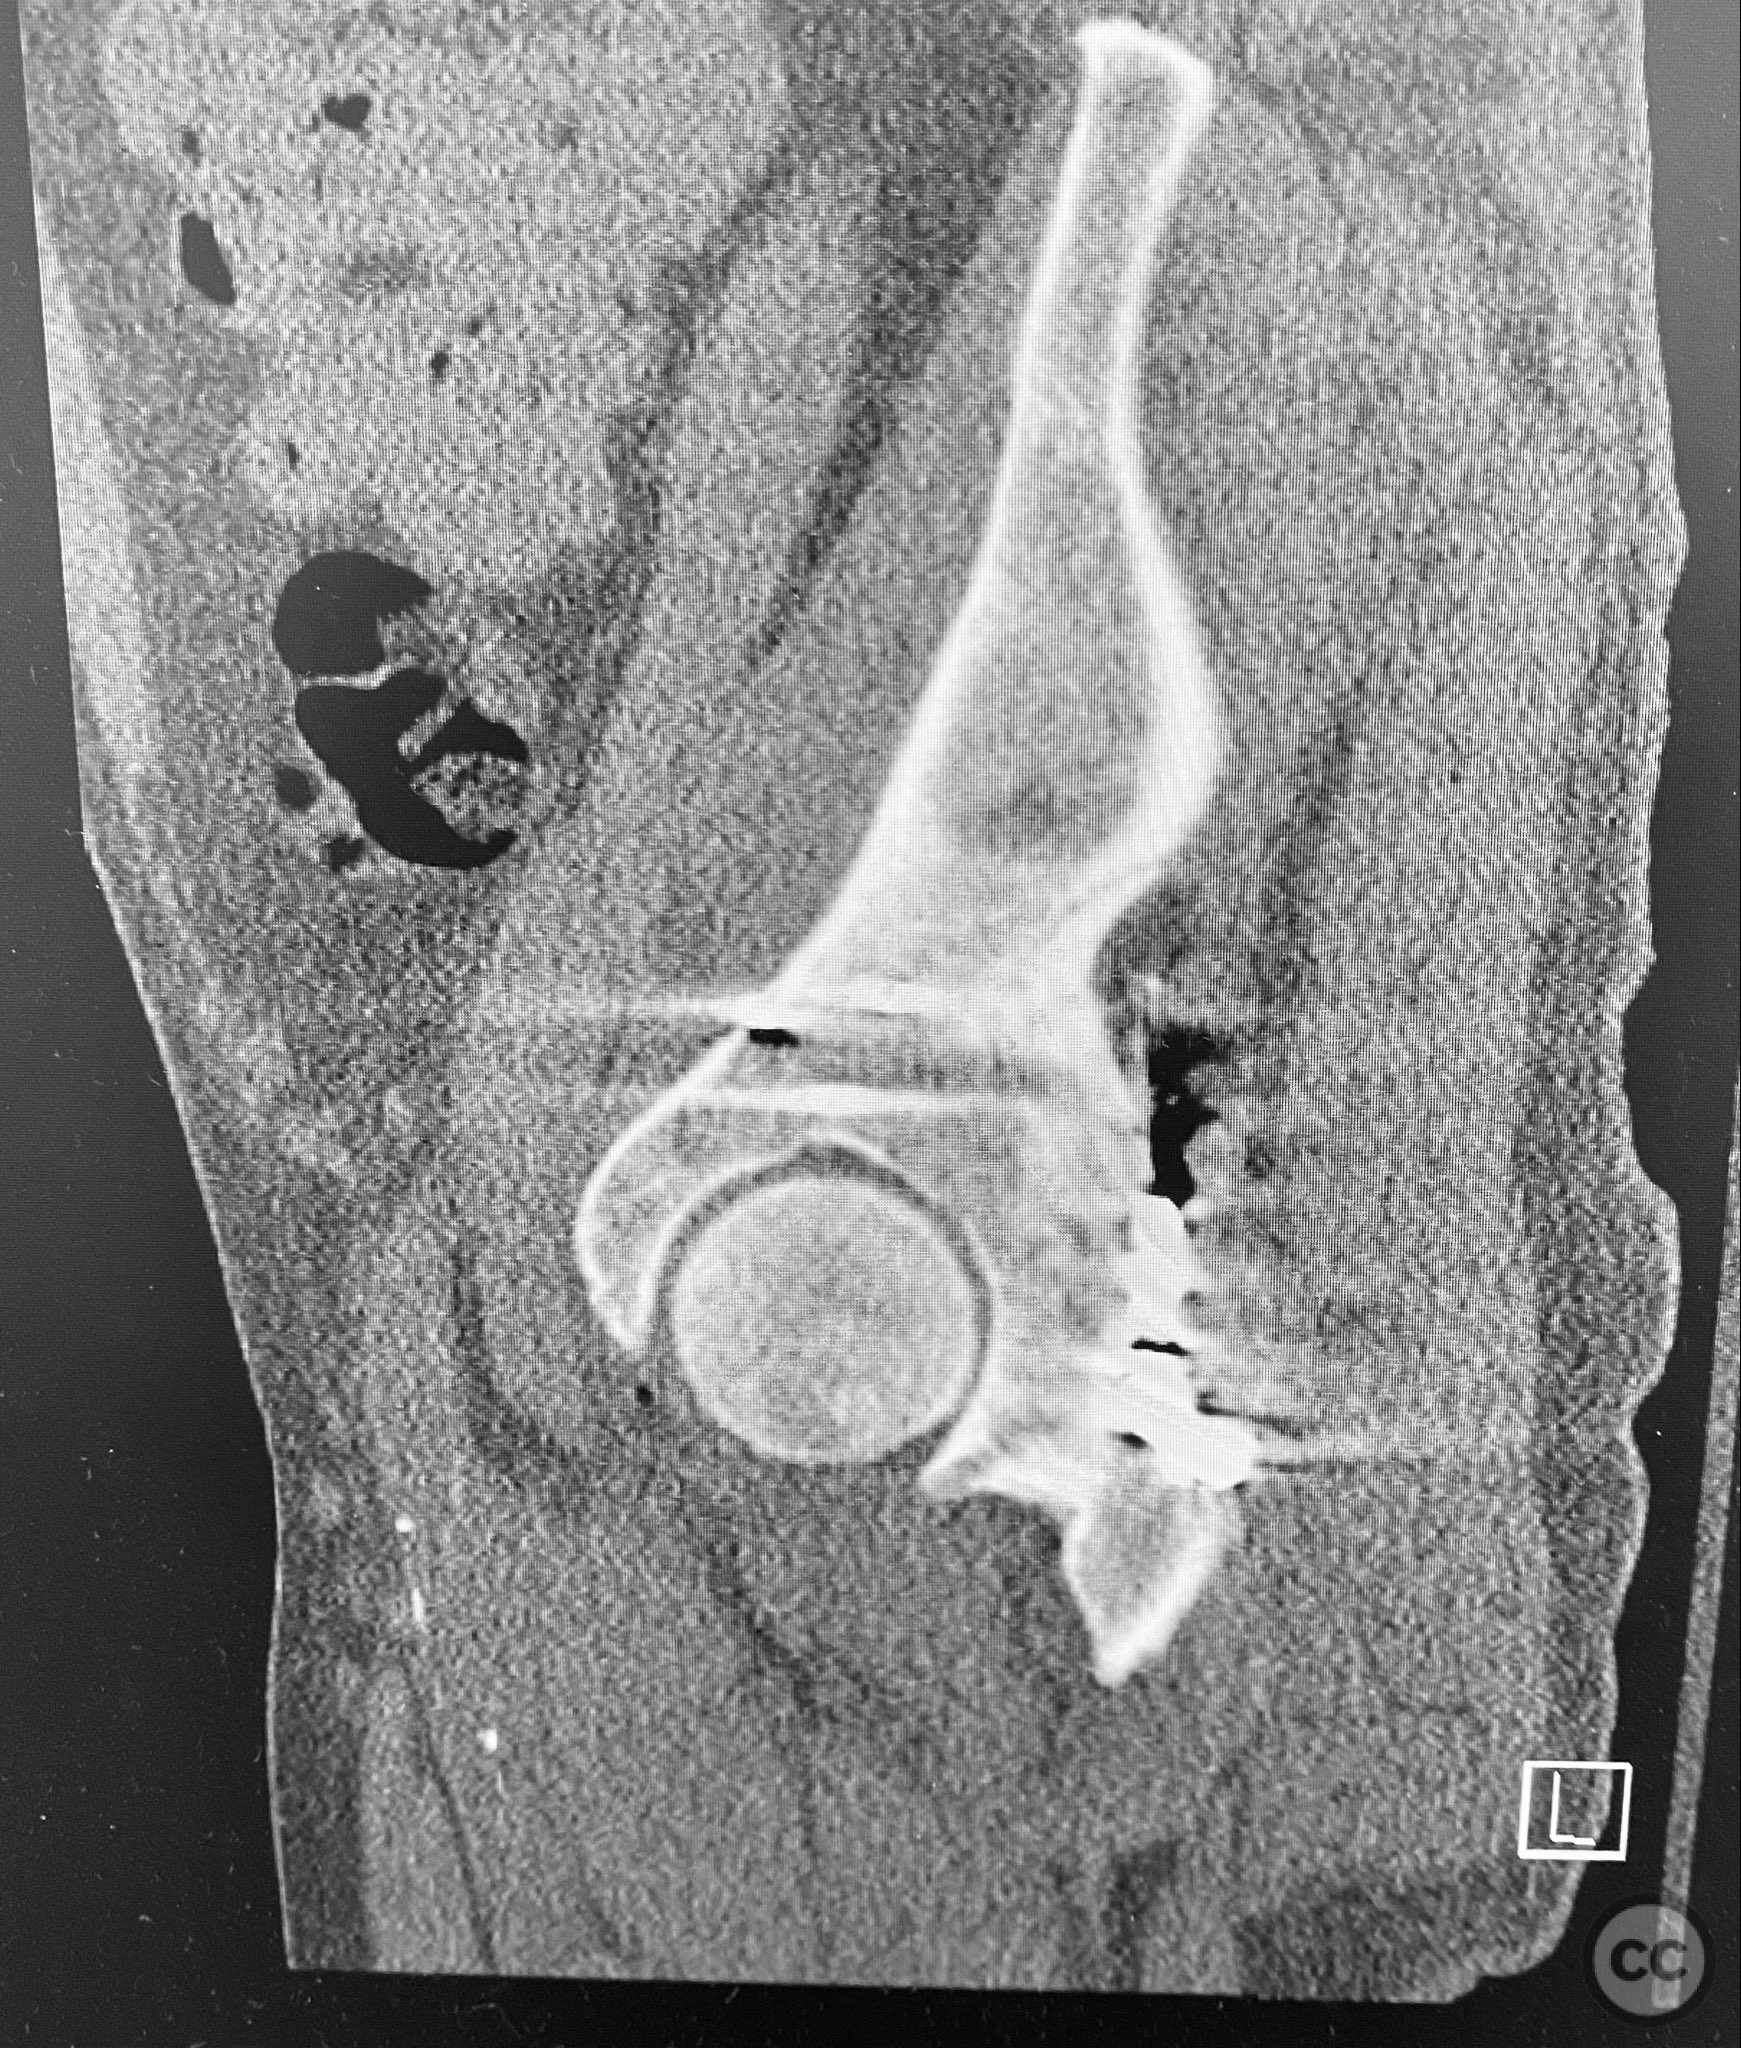

Clinical and radiological findings:  A patient presented with a seemingly non-comminuted, wide, and long posterior wall (PW) acetabular fracture fragment. Axial computed tomography (CT) images demonstrated the thickness of the PW fragment, the articular surface, and multiple areas of subchondral impaction. Preoperative planning identified the size, location, and depth of the impaction zones, as well as an essentially nondisplaced transverse acetabular fracture line, which was not readily apparent on initial imaging. No significant displacement of the transverse component was noted. The AO/OTA classification is 62-B1.3 (posterior wall and transverse acetabular fracture).

Planning remarks:  The preoperative technical plan included a prone Kocher-Langenbeck (KL) approach to access the posterior column and wall. The plan entailed elevation and reduction of impacted articular fragments, bone grafting of subchondral defects, anatomical reduction and provisional fixation of the posterior wall fragment, and definitive fixation with a contoured plate. Intraoperative fluoroscopy was planned to guide additional screw placement through the plate to stabilize both the posterior wall and the transverse fracture line. A supplementary medial plate was planned to augment fixation of both the posterior wall and transverse components.

Intraoperatively, elevation and reduction of impacted articular fragments were performed, followed by bone grafting of subchondral defects. The posterior wall fragment was anatomically reduced and initially stabilized with a contoured plate. Intraoperative fluoroscopy (obturator oblique view) was utilized to guide placement of an additional screw through the plate above the joint, traversing both the posterior wall fragment and stabilizing the transverse fracture line. A supplementary medial plate was applied to further support both fracture components. Postoperative CT imaging confirmed satisfactory reduction of both the posterior wall and transverse fractures, as well as restoration of articular congruity in previously impacted areas. Consideration is given to whether initial reduction and lag screw fixation of the transverse component prior to plate application may have improved reduction; however, final imaging demonstrated acceptable alignment.